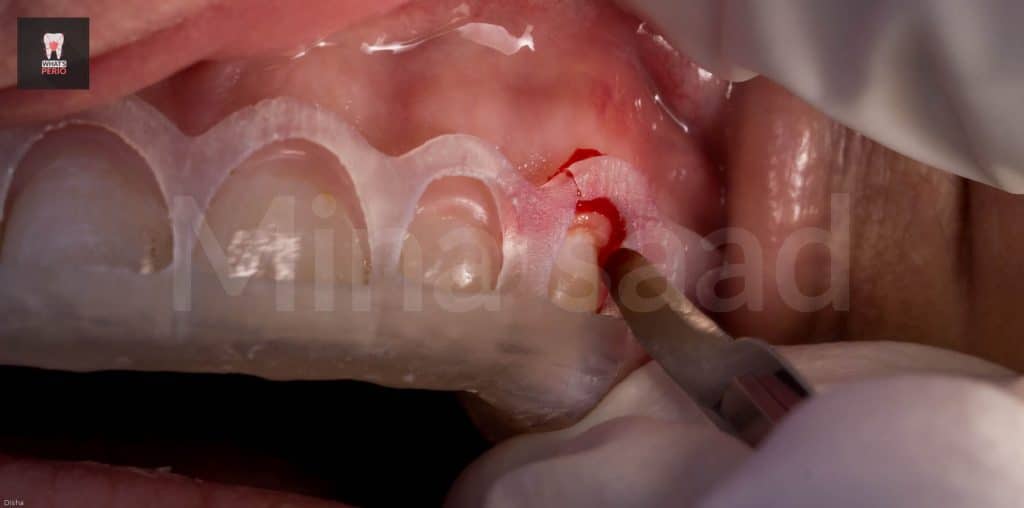

-Ostectomy was made using a rose head diamond stone then the guide was put in place again & it was observed that the apical level & the alveolar crest is at the same level now.

-A periodontal probe was placed between CEJ & alveolar crest to measure the distance which was 2mm. “ensuring that the digital guide is accurate”

-Prominence of canine eminence of the right side was observed to more bulky than the left one . “this was confirmed clinically & radiographicaly in occlusal view of CBCT”

-Osteoplasty wass performed to reshape the prominent canine eminence to be in harmony with the left one & in general the labial plate of bone was shaped & any sharp angles resulting from ostectomy procedure were removed for better adaptation of the flap ensuring nice healing results.